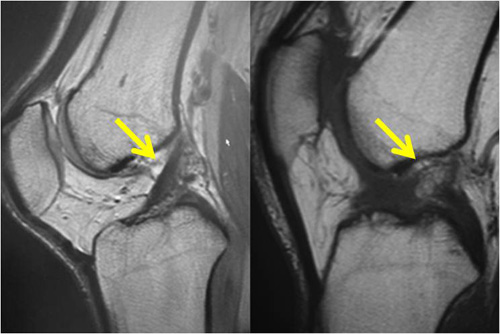

再建靱帯は、人工靭帯を一部に使用し、関節内の部分は自分の腱を使い、骨の中や関節の外の部分には人工靱帯を使って、取る腱の長さが最小限で済むようにしています。当院では、損傷靱帯の状態によって、1本ないし2本の再建靱帯を通します。

左:正常 右:再建したACL